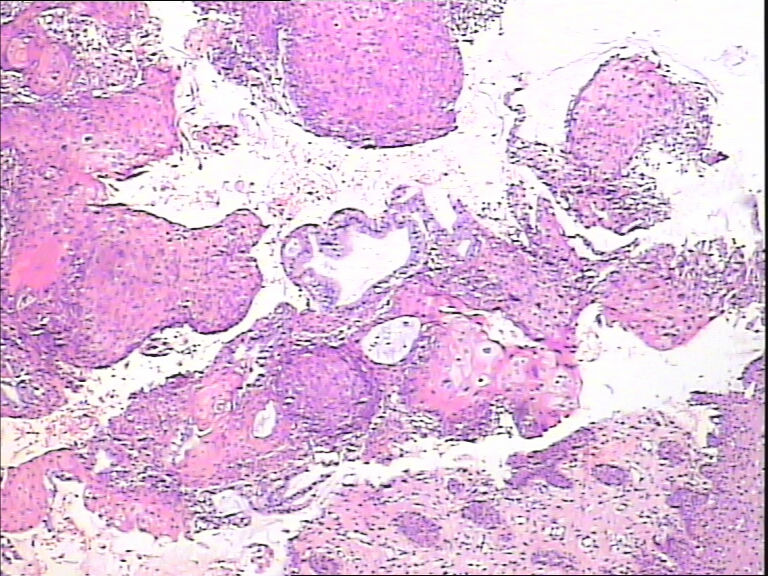

45y,触血,宫颈多点活检。

考虑HPV感染,应该没有高级别上皮内瘤变,建议做HPV检测。

CINⅡ,提示HPV感染。

慢性宫颈炎伴HPV感染改变、腺体鳞状化生。

湿疣改变

HPV感染。局部已达到CIN2-3

主要考虑HPV感染引起的细胞改变。

HPV感染。灶性CIN2-3

HPV感染

不同级别的CIN,局灶已达到CIN3。

HSIL伴